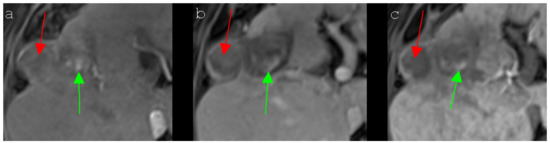

Figure 5. A 67-year-old man with a local tumor progression in the peripheral ablation zone (segment VIII/Iva) six months after IRE of an HCC, which presented atypical signal behavior in Gd-EOB-DTPA-based MR imaging. The nodular, exophytic HCC (red arrow) showed a slight peripheral enhancement and a central hypointensity in the contrast-enhanced T1 arterial phase MR image (a), the typically known hypervascularization was lacking, however. The signal intensities of the HCC remained unchanged during the contrast-enhanced T1 portal venous phase (b) and the contrast-enhanced T1 delayed phase MR image (c). A typical “wash-out” could not be observed. The central part of the ablation area showed several hyperintense spots (green arrow), which could be detected in all presented MRI sequences (ac), attributable to post-interventional hemorrhagic transformation.